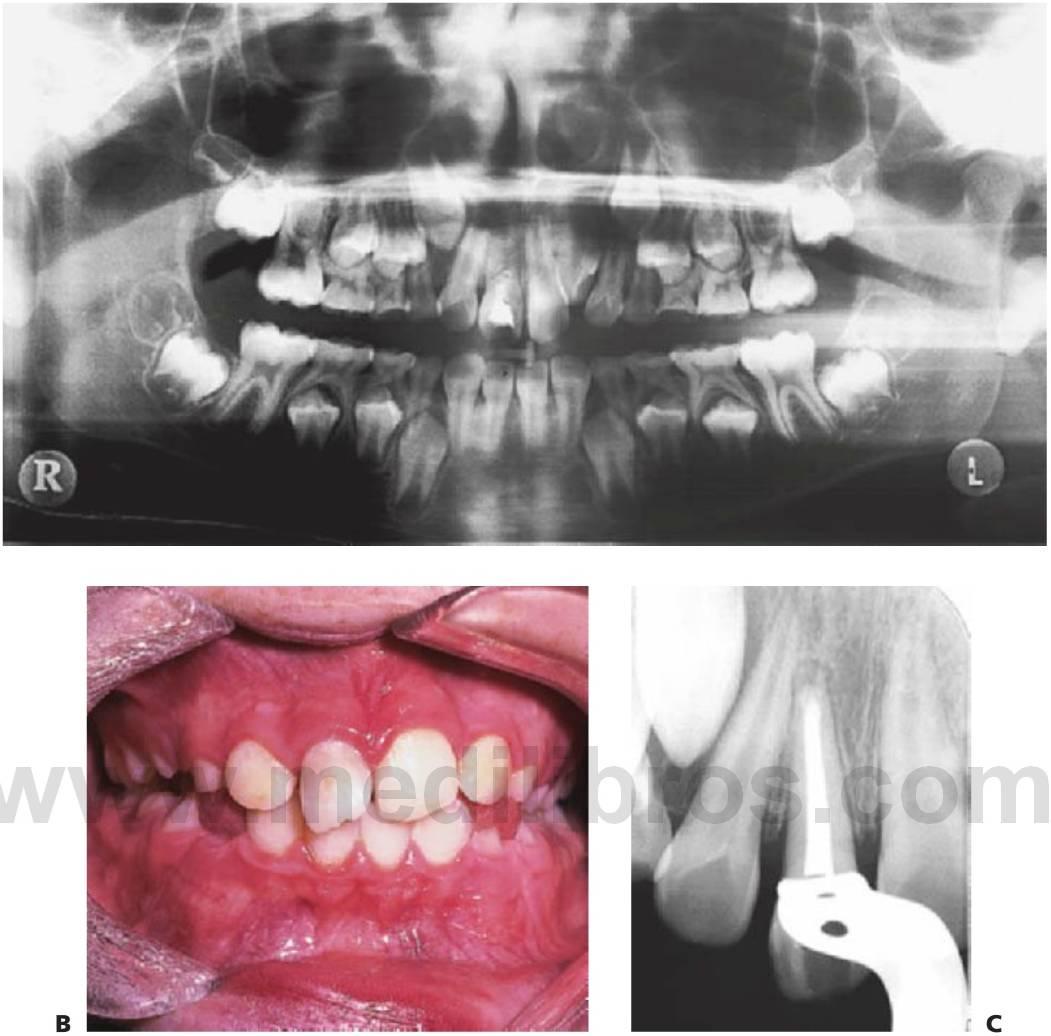

Las fracturas de los huesos faciales no son habituales en niños y representan menos del 5% del total de las fracturas maxilofaciales. En consecuencia, pocos cirujanos presentan una vasta experiencia en esta área, si bien el enfoque que hagan de estos casos deberá valorar las implicaciones de dichas lesiones en el crecimiento del niño (fig. 7.7).

Puede que las fracturas del cóndilo mandibular se infradiagnostiquen en niños, pero suponen hasta dos tercios del total de las lesiones mandibulares y por lo general, suelen producirse por un traumatismo en el borde inferior del mentón. Si se produce una fractura subcondílea, la cabeza del cóndilo se desplaza de forma anteromedial por acción del músculo pterigoideo lateral. Dependiendo del desplazamiento de los fragmentos y de la postura compensatoria de la mandíbula, podría producirse una desviación del mentón hacia el lado afectado, no producirse desarmonías oclusales y quizá un sangrado desde el meato externo, debido a la perforación con la cabeza del cóndilo de la pared anterior del conducto auditivo (v. fig. 7.7C, D). Un otorrinolaringólogo deberá estudiar el sangrado o la secreción desde el oído, pero está contraindicada la succión del meato externo debido a la potencial alteración de la cadena osicular, que podría ocasionar la perforación de la membrana timpánica. Se ha citado algún caso de desplazamiento de la cabeza del cóndilo hacia la fosa craneal media pero es infrecuente.

Debido a que el cuello del cóndilo es relativamente más ancho en los niños y tiene un volumen mayor de hueso esponjoso, las fracturas de la superficie articular son más habituales que en los adultos. En los casos de fractura intracapsular (figs. 7.5, 7.9), el seguimiento durante años permite detectar cualquier alteración de su crecimiento, y en los casos en que aparezca una limitación de la apertura o una anquilosis franca, se recomienda una intervención temprana con un injerto costocondral.